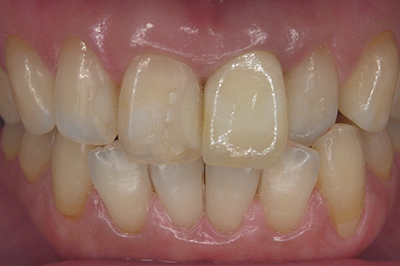

治療例1

| ご費用 | 手術費用人工歯根 1本275,000円(税込) 上部構造 88,000円~110,000円(税込) |

|---|---|

| リスク・副作用 |

保険非適応(自費診療) 特定の全身疾患や持病のある方、顎骨密度の足りない方、妊娠中の方は手術ができない場合があります。 下顎のインプラント手術の際、偶発症のリスクがあります。 人工歯根が顎骨と癒着しないリスクがあります。 インプラント周囲炎になるリスクがあります。 |